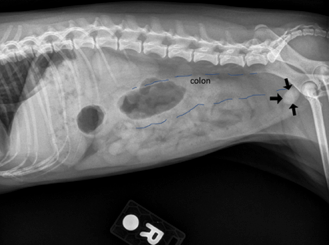

On this right lateral view, there was an ovoid mineral opaque object at the anatomic location of urinary bladder. According to the radiologist, it was a single bladder stone (pointed by black arrows) which was consistent with Sissy’s history. There was reginal poor serosal detail in the cranial abdomen. The colon was filled with gas and soft tissue opaque fluid (outlined by blue dashes) which was consistent with diarrhea history.